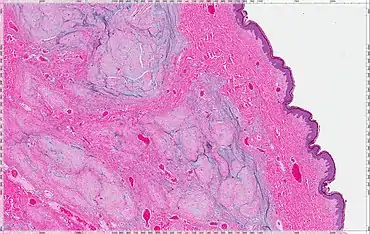

| Micrograph of an atrial myxoma. H&E stain. | |

A myxoma (New Latin from Greek muxa 'mucus') is a myxoid tumor of primitive connective tissue.[1] It is most commonly found in the heart (and is the most common primary tumor of the heart in adults) but can also occur in other locations.